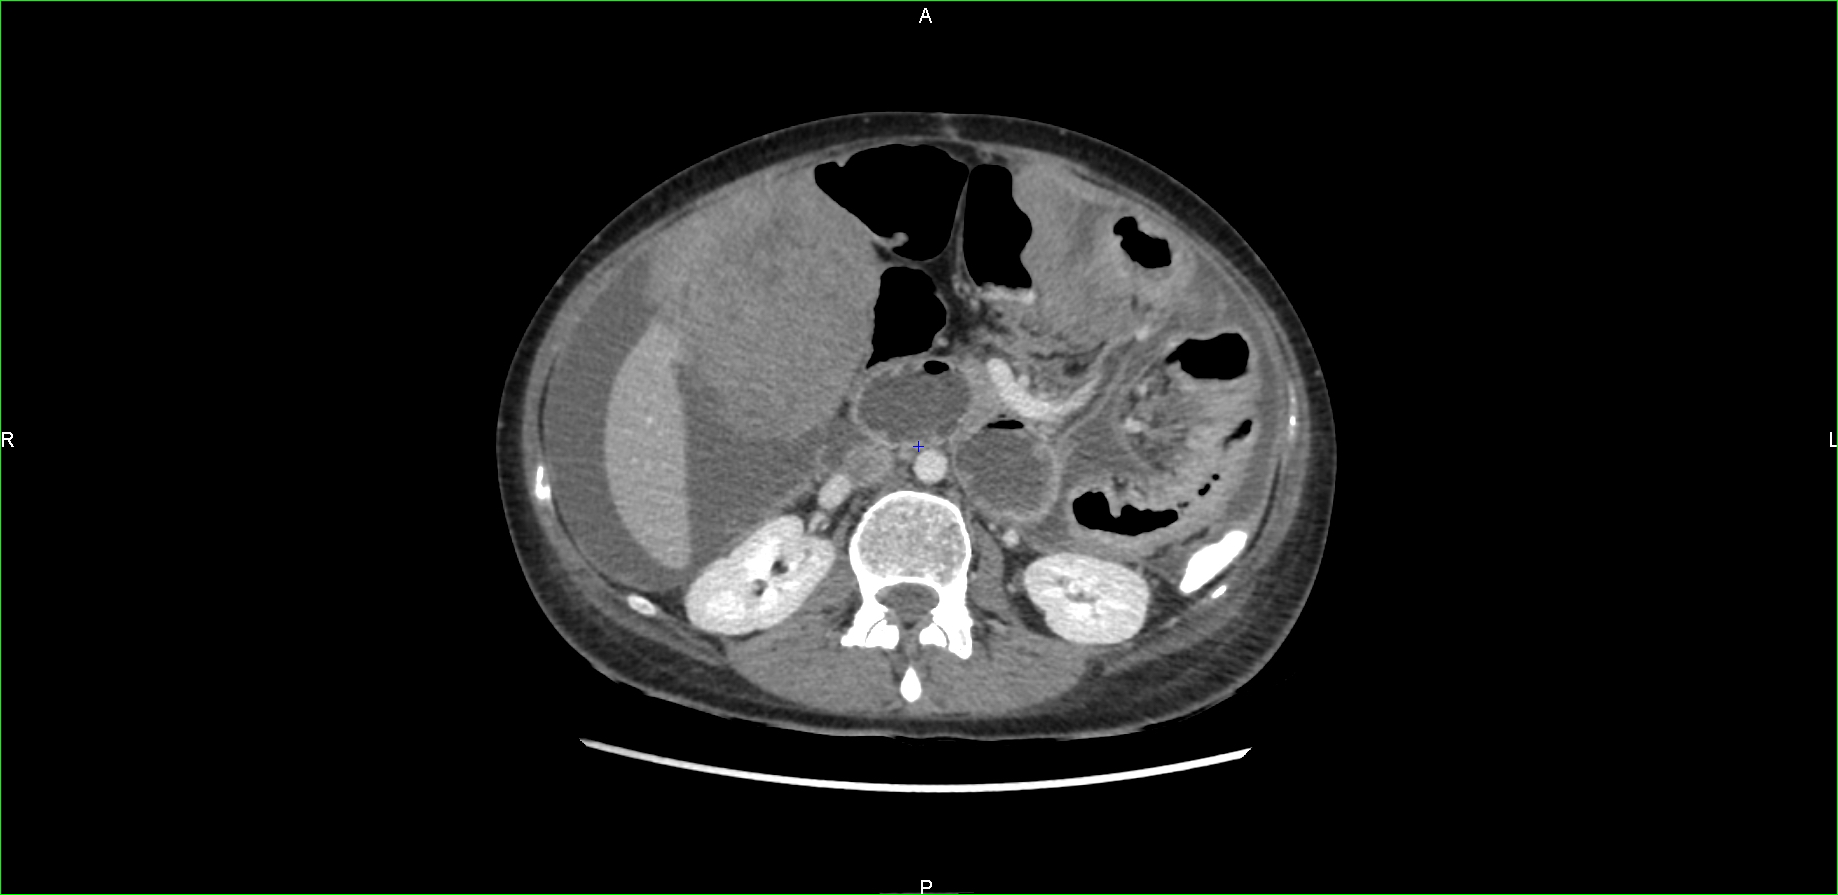

Treatment with imatinib was initiated because of suspect lesions on an early CT scan ordered for abdominal discomfort. Three months later, as the patient suffered refractory intestinal obstruction, abdominal pain, and deterioration in general condition, imaging was obtained showing rapid progression with peritoneal and liver metastases associated with tumoral ascites (Figure 1).

Figure 1

CT scan showing early and massive relapse.